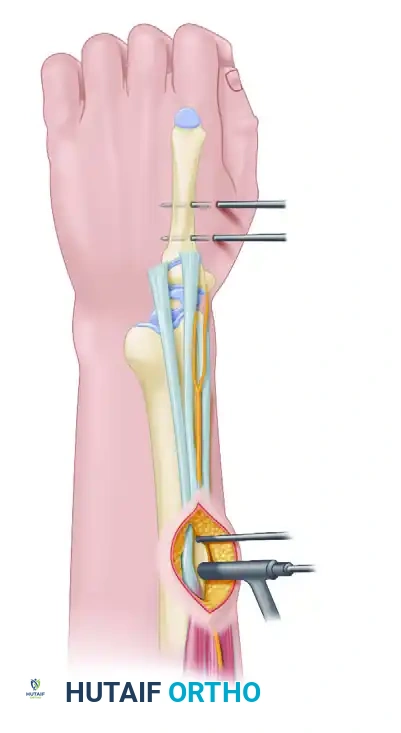

EXTERNAL FIXATION OF THE DISTAL RADIUS

External fixation serves as an excellent primary or adjunctive treatment for specific distal radial fractures, particularly those with severe soft tissue injury, highly comminuted intra-articular extensions (spanning fixation), or in damage-control orthopedics.

Bridging vs. Non-Bridging External Fixation

- Bridging External Fixation: The frame spans the radiocarpal joint, with pins placed in the radius proximally and the second metacarpal distally. This utilizes ligamentotaxis to maintain reduction.

- Non-Bridging External Fixation: Consists of a distal pin cluster inserted directly into the distal radial fragment without crossing the wrist joint. McQueen has reported extensively on this technique for extra-articular fractures that demonstrate enough distal bone stock to accept the pins. While results are excellent in properly selected patients, it requires a relatively large, intact distal fragment, limiting its widespread use.

Surgical Technique: Bridging External Fixation

- Metacarpal Pin Placement: Make two small incisions over the dorsoradial aspect of the second metacarpal. Bluntly dissect to the bone to protect the dorsal sensory branches of the radial nerve and the extensor tendons. Insert two 3.0-mm or 3.2-mm half-pins into the base and midshaft of the second metacarpal, ensuring bicortical purchase.

- Radial Pin Placement: Make two incisions over the dorsoradial aspect of the radius, approximately 10 cm proximal to the fracture site (between the extensor carpi radialis longus and brachioradialis). Bluntly dissect to the bone, use a drill sleeve, and insert two 3.0-mm or 4.0-mm half-pins bicortically.

- Frame Assembly: Connect the pins using a single-bar or double-bar carbon fiber frame.

- Reduction and Locking: Apply longitudinal traction to the hand to achieve ligamentotaxis. Correct volar tilt manually. Once the reduction is confirmed fluoroscopically, tighten the clamps to lock the frame.

The Critical Role of Supplemental Fixation

As previously noted, linear traction typically does not fully restore volar tilt; however, a neutral tilt is clinically acceptable. Wei et al. reported good functional results with external fixation provided satisfactory reduction is obtained and maintained.

Because the external fixator alone cannot prevent micromotion and subsequent shortening in comminuted fractures, supplemental fixation with percutaneous K-wires is strongly recommended. The K-wires secure the articular fragments and maintain radial height, while the fixator neutralizes the deforming forces of the forearm musculature.

Clinical Pearl: We rarely apply definitive external fixation without the use of supplemental Kirschner wires. In cases of severe metaphyseal void, the addition of bone graft or bone graft substitutes can also be highly beneficial to prevent late collapse.